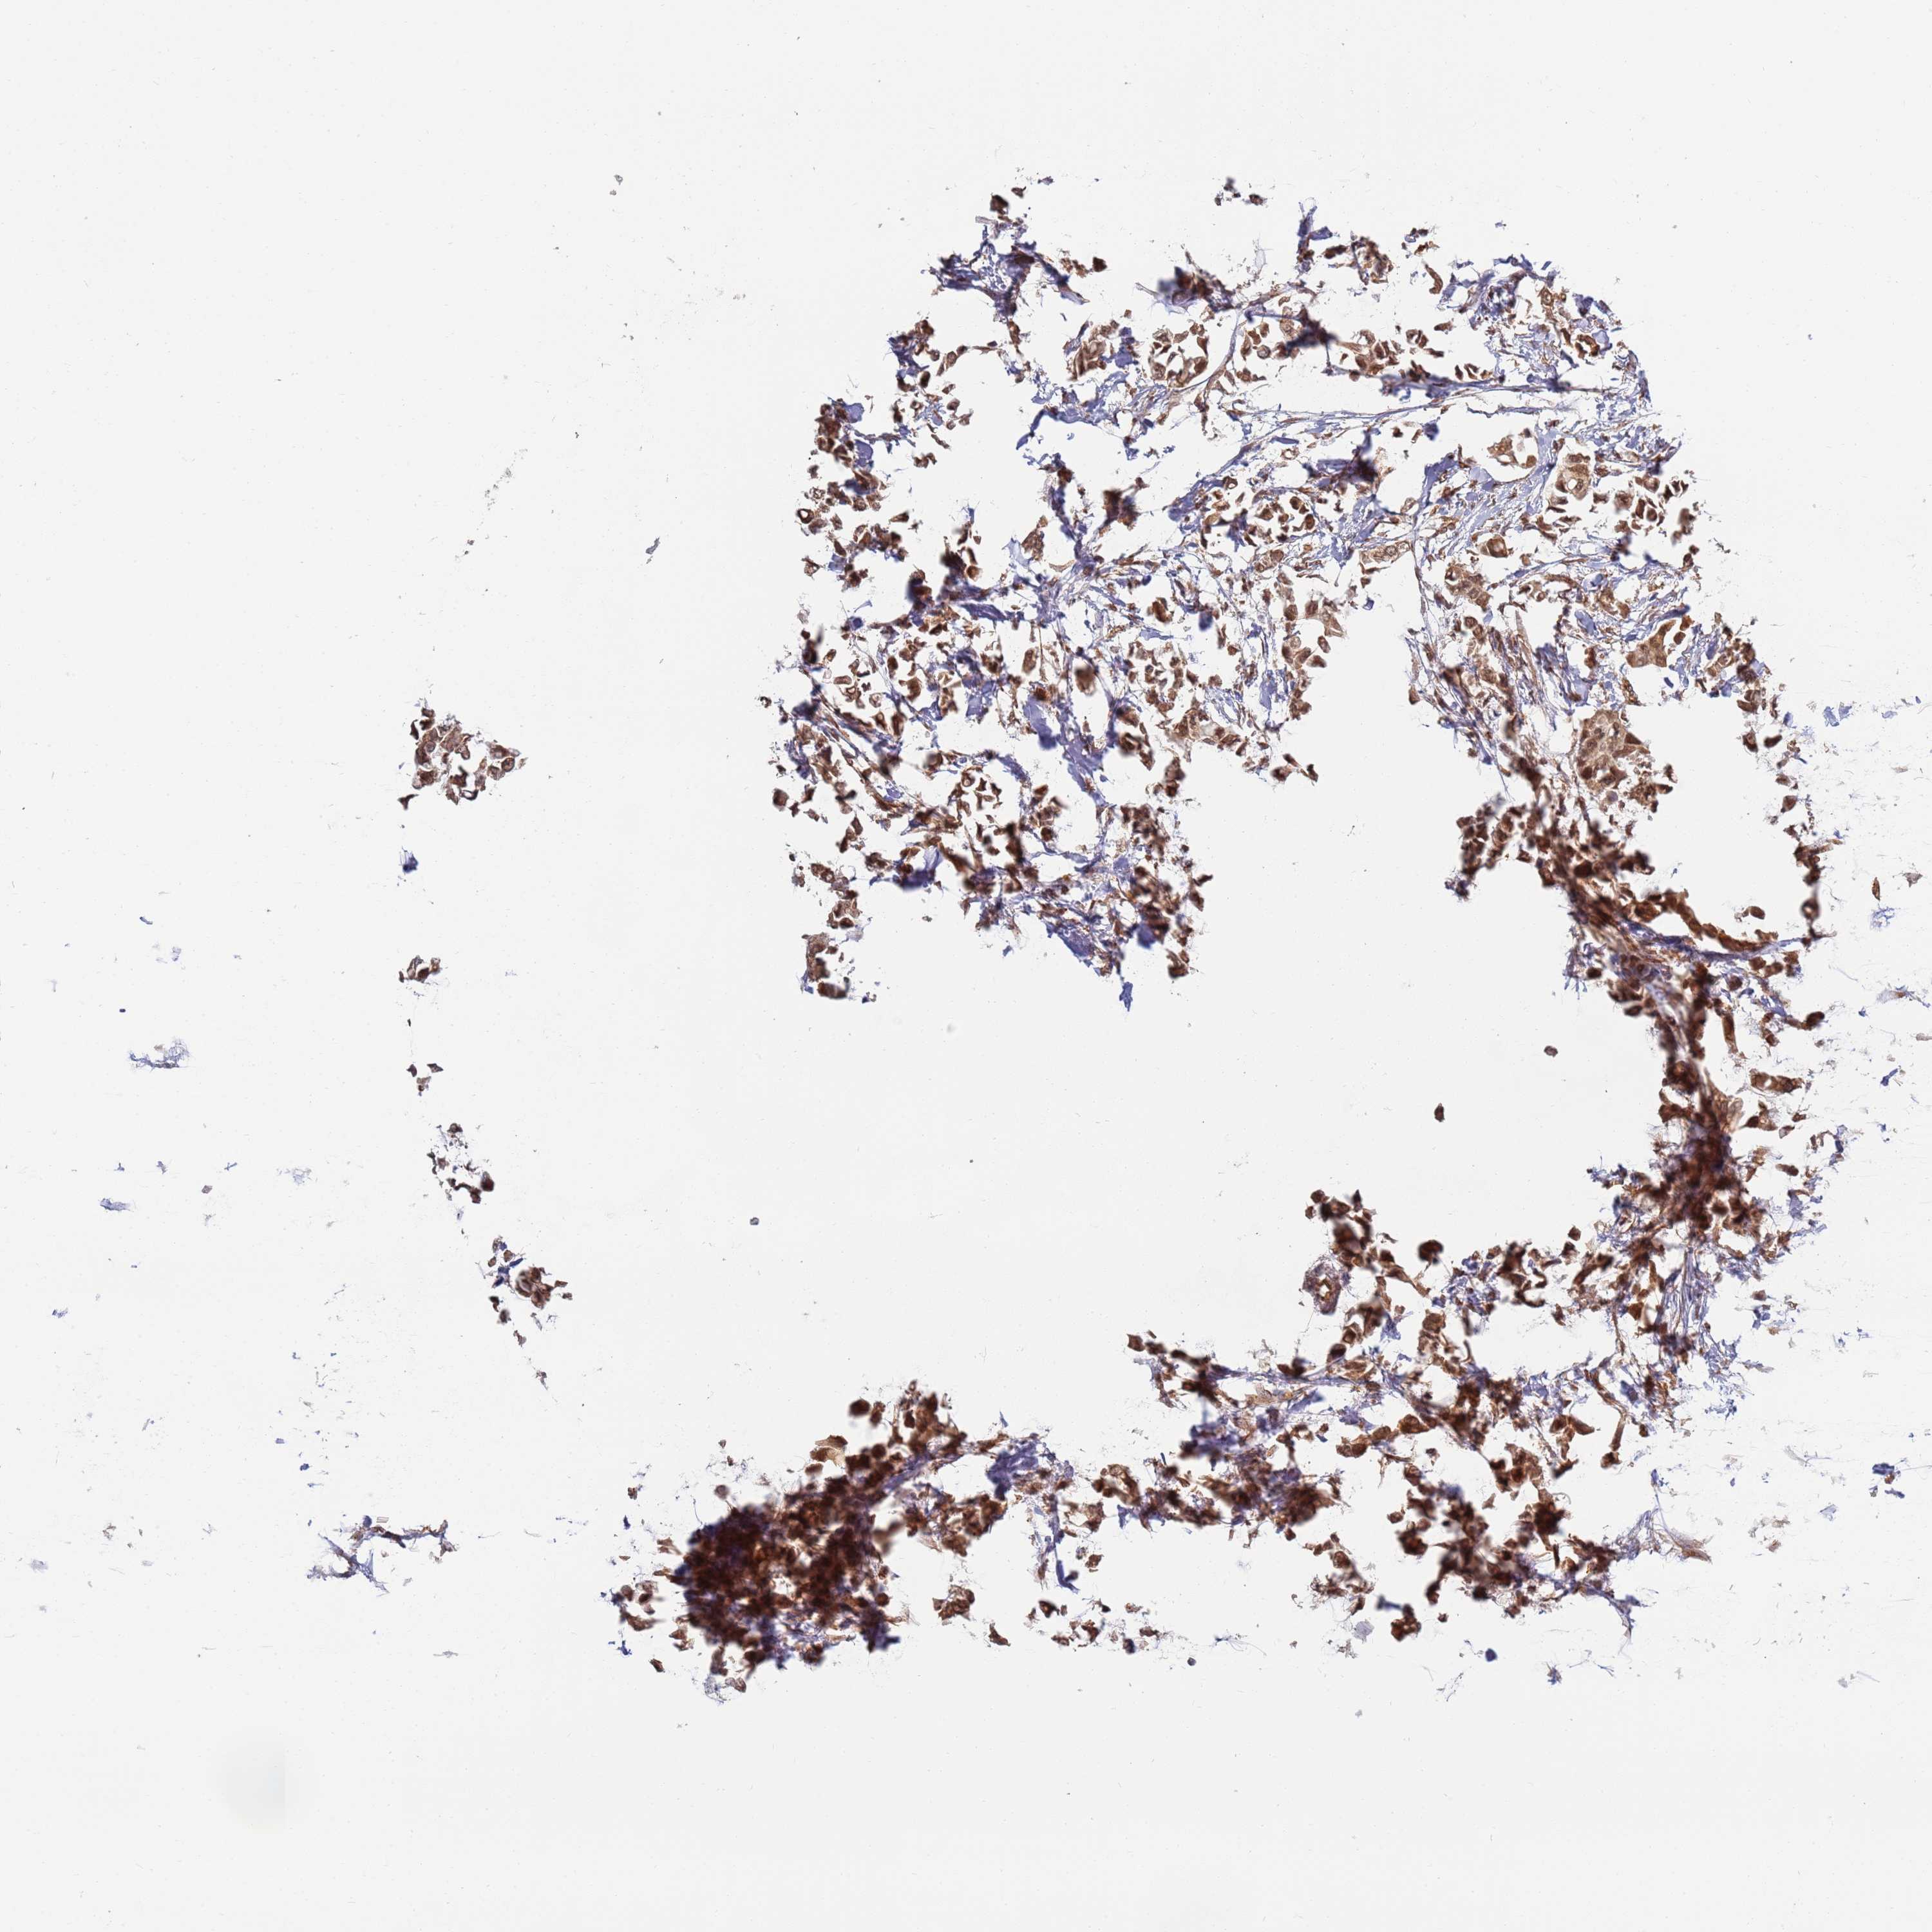

CANCER BREAST CANCER Show tissue menu

BRCA TCGA BRCA VALIDATION PROTEIN EXPRESSION

ANTIBODIES

AND

VALIDATION